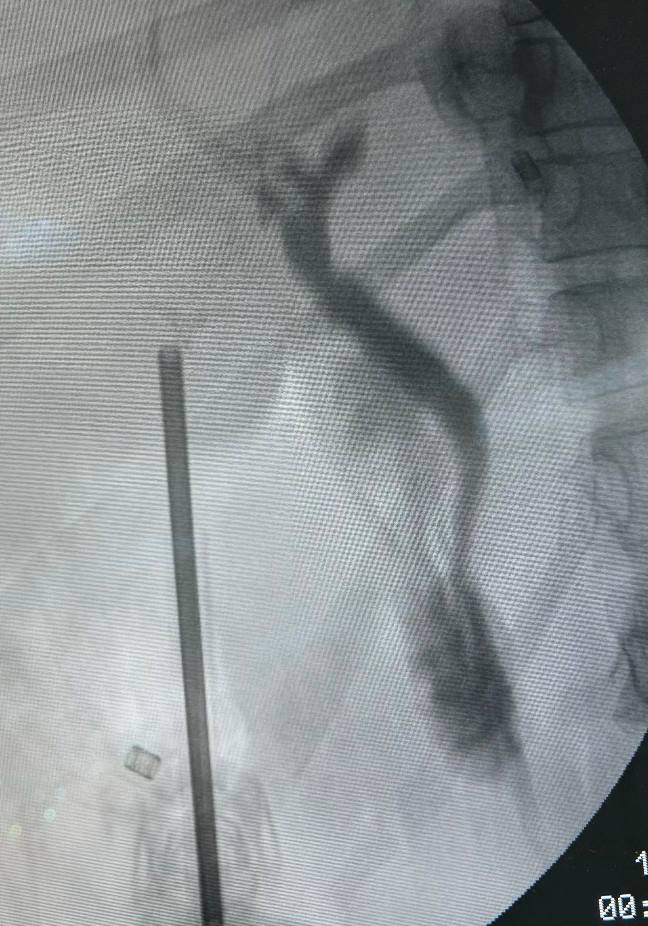

IOC de litíase

O diagnóstico é feito por um médico especializado, que pode solicitar exames como ultrassom ou ressonância magnética. Dependendo dos resultados e dos sintomas, o médico pode recomendar a cirurgia.